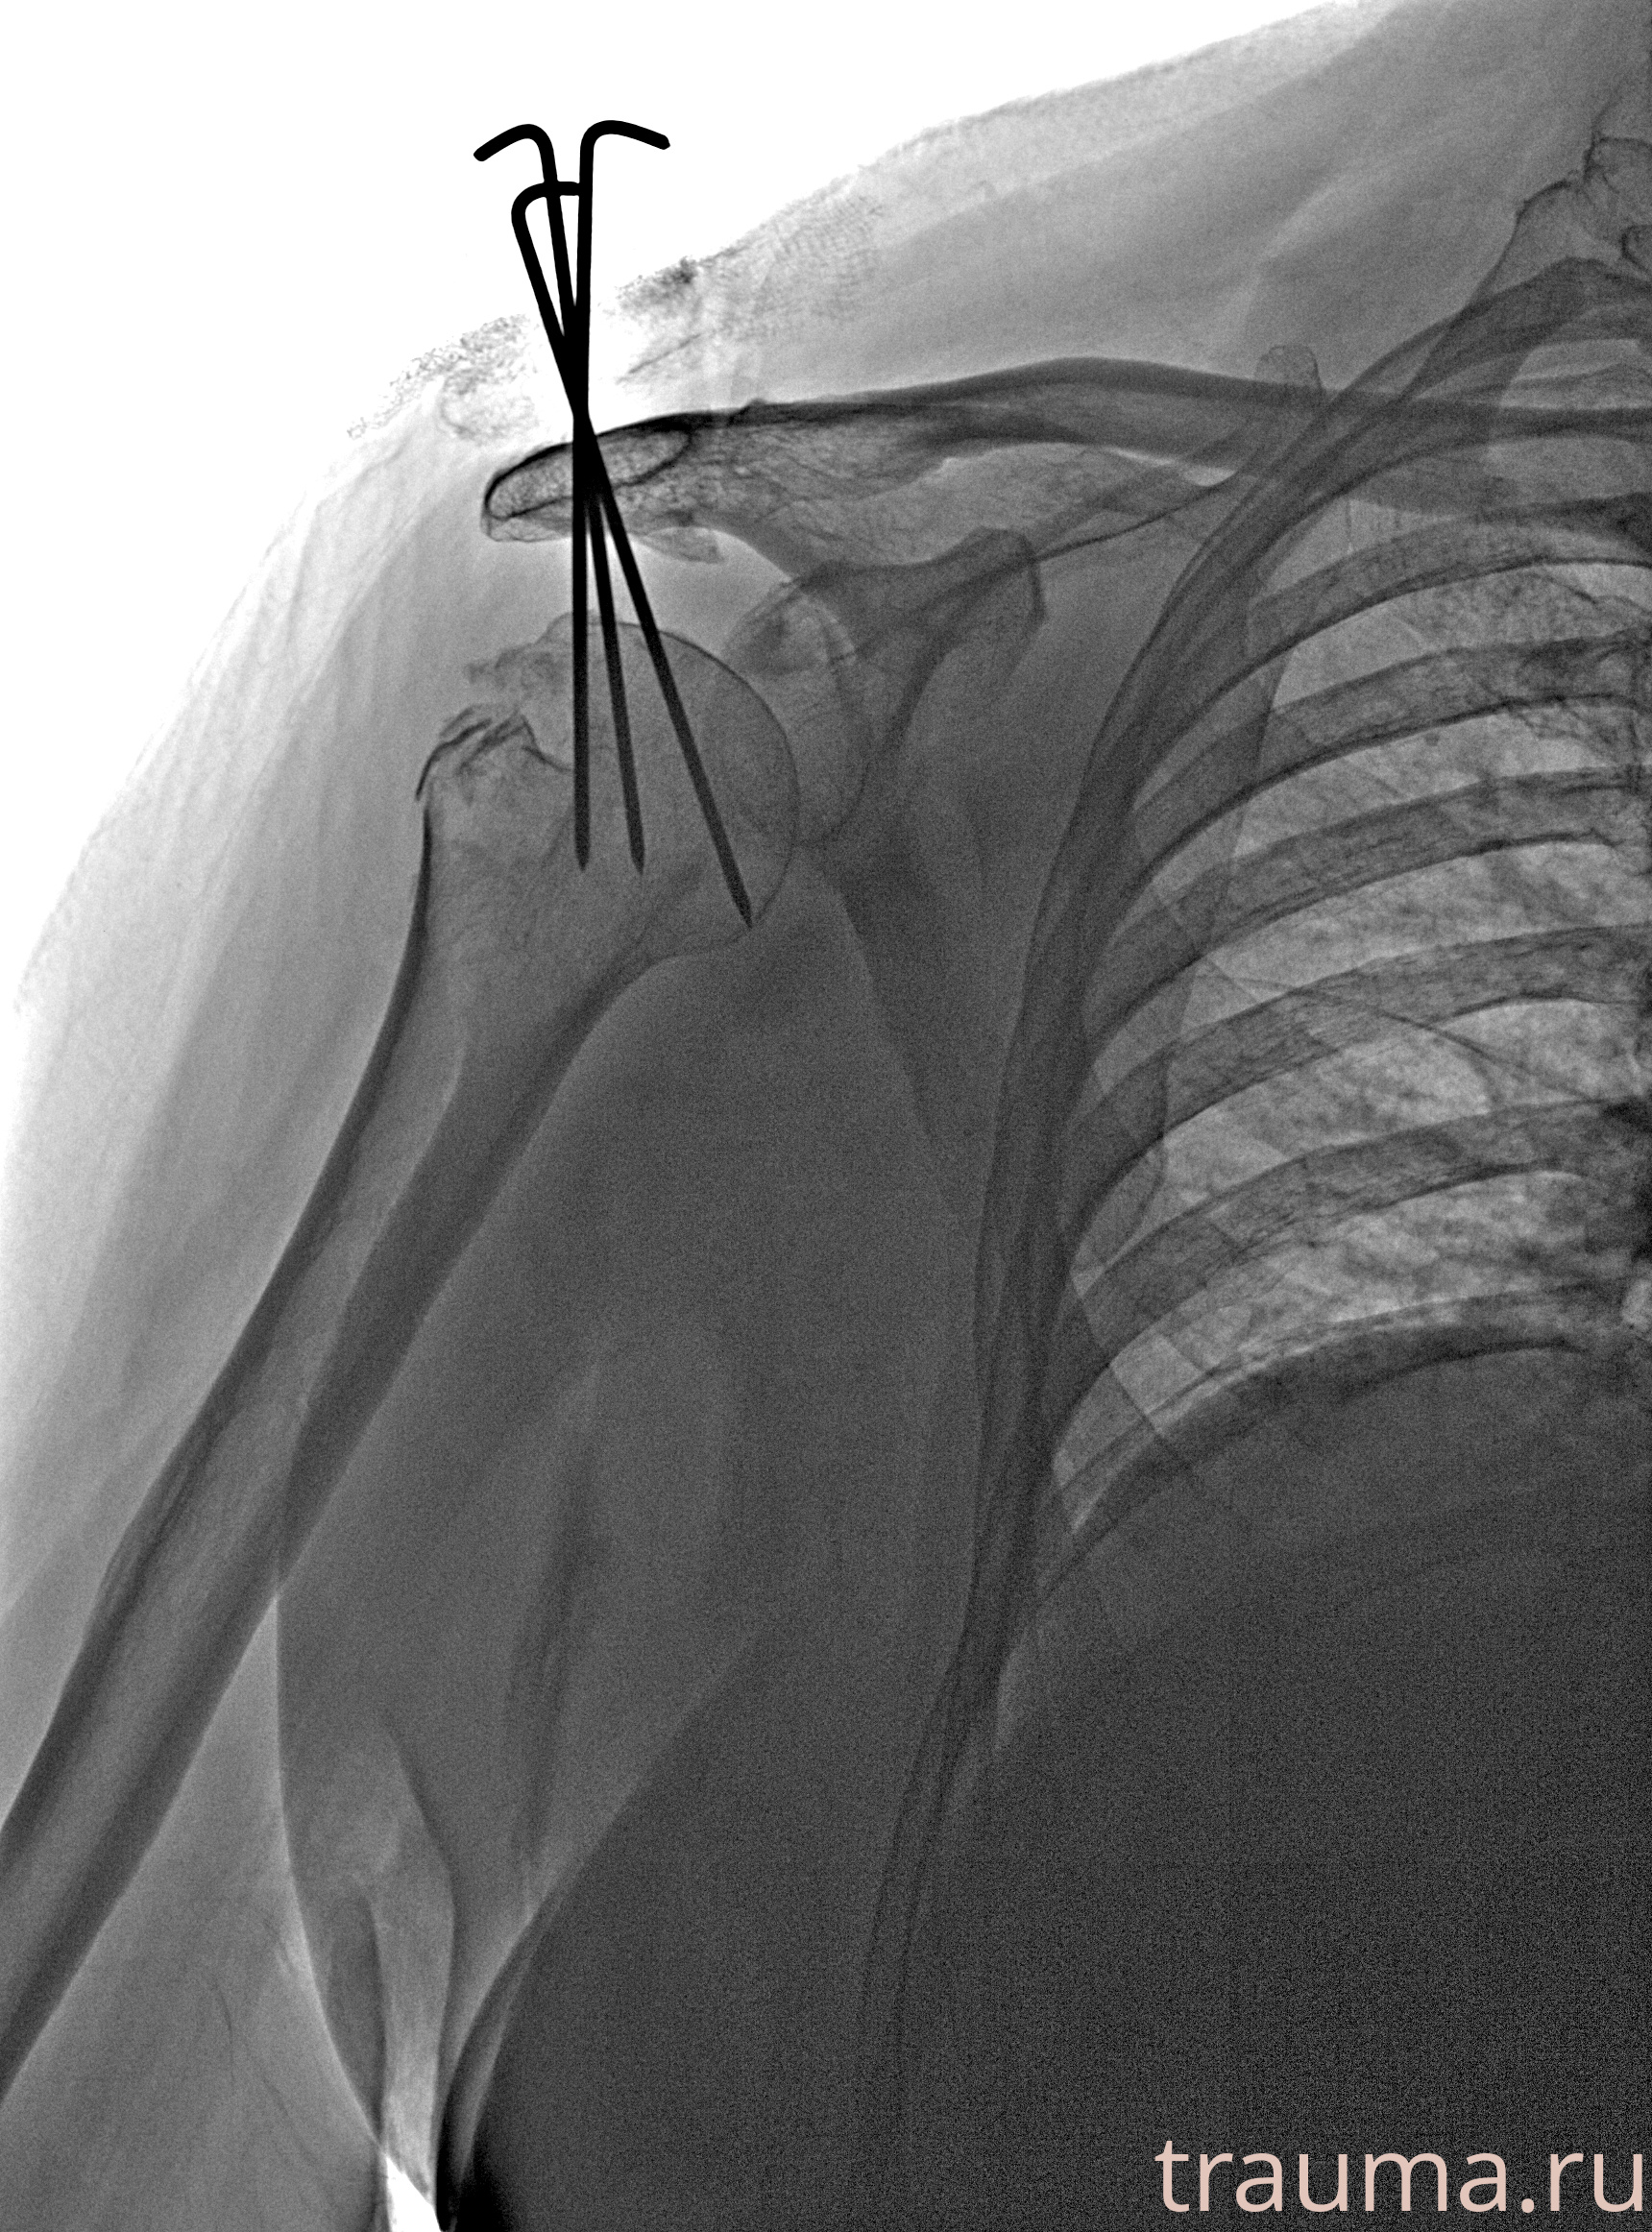

Рентгенограммы

Рентген на дому: по вашему адресу приезжает врач-рентгенолог, травматолог-ортопед с мобильным рентгеновским аппаратом, проводит диагностику травмы или заболевания, делает необходимые рентгенограммы, дает рекомендации по дальнейшему лечению. Получить качественные снимки в домашних условиях возможно благодаря уникальной методике, разработанной МосРентген Центром для института  Склифосовского